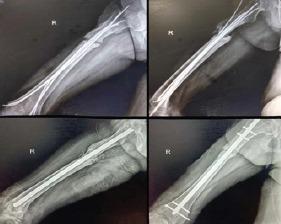

A 25-year-old female patient presented with pain and swelling over the anterolateral aspect of the right thigh after a traumatic road traffic accident 2 days back. On radiological investigation, there was subtrochanteric femur fracture with a butterfly fragment. The patient also had Morel-Lavallee lesion on local ultrasound. Emergency management was done for Morel-Lavallee lesion in the form of percutaneous drainage and compression bandage; fixation was done in the form of external fixator. The wound progressed into complete skin necrosis so external fixator was removed and thorough wound debridement was done. Fracture stabilized with four TENS nails (titanium elastic nail). Removal of the TENS nail and exchange nailing in the form of intramedullary interlocking nail was performed after complete soft-tissue healing. Bony union seen at the fracture site clinically and radiologically at 3-month follow-up.

一名25岁女性患者在2天前发生道路交通事故后,出现右大腿前外侧疼痛和肿胀。经影像学检查,发现股骨转子下骨折并伴有蝶形骨块。患者在局部超声检查中还发现有莫雷尔-拉瓦利损伤。对莫雷尔-拉瓦利损伤进行了急诊处理,采用经皮引流和加压包扎;以外部固定器的形式进行固定。伤口发展为完全皮肤坏死,因此拆除了外部固定器并进行了彻底的伤口清创。用四根TENS钉(钛弹性钉)使骨折稳定。在软组织完全愈合后,取出TENS钉并以髓内交锁钉的形式进行更换钉。在3个月的随访中,骨折部位在临床和影像学上均可见骨愈合。